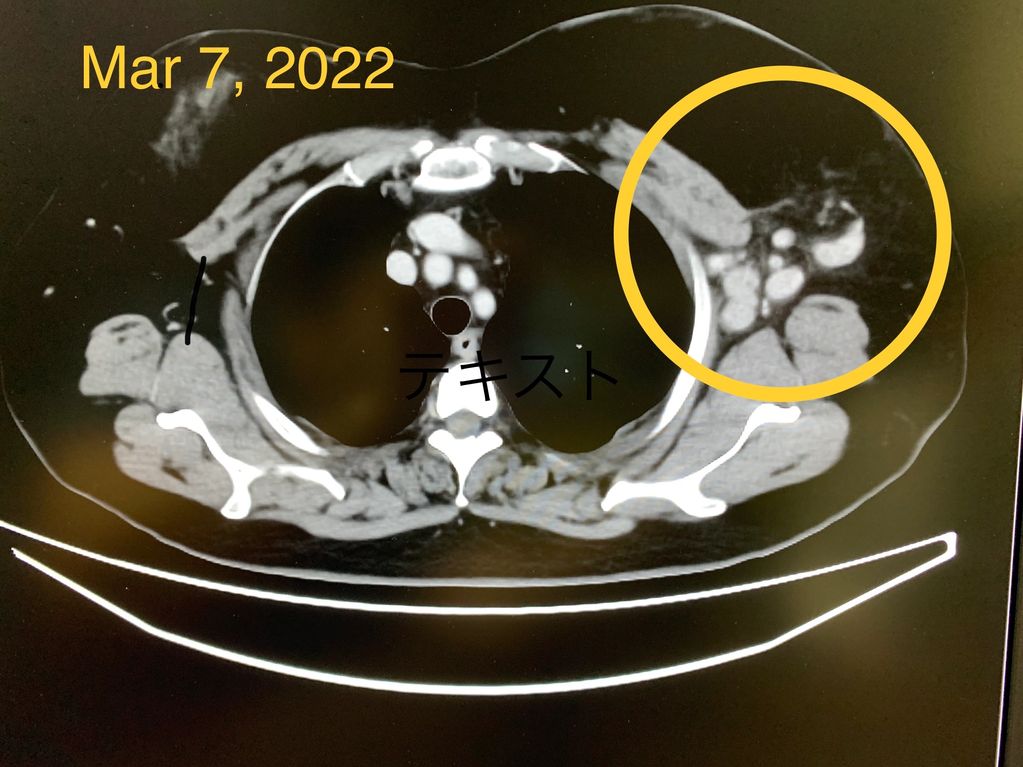

Prior CT scan before treatment.